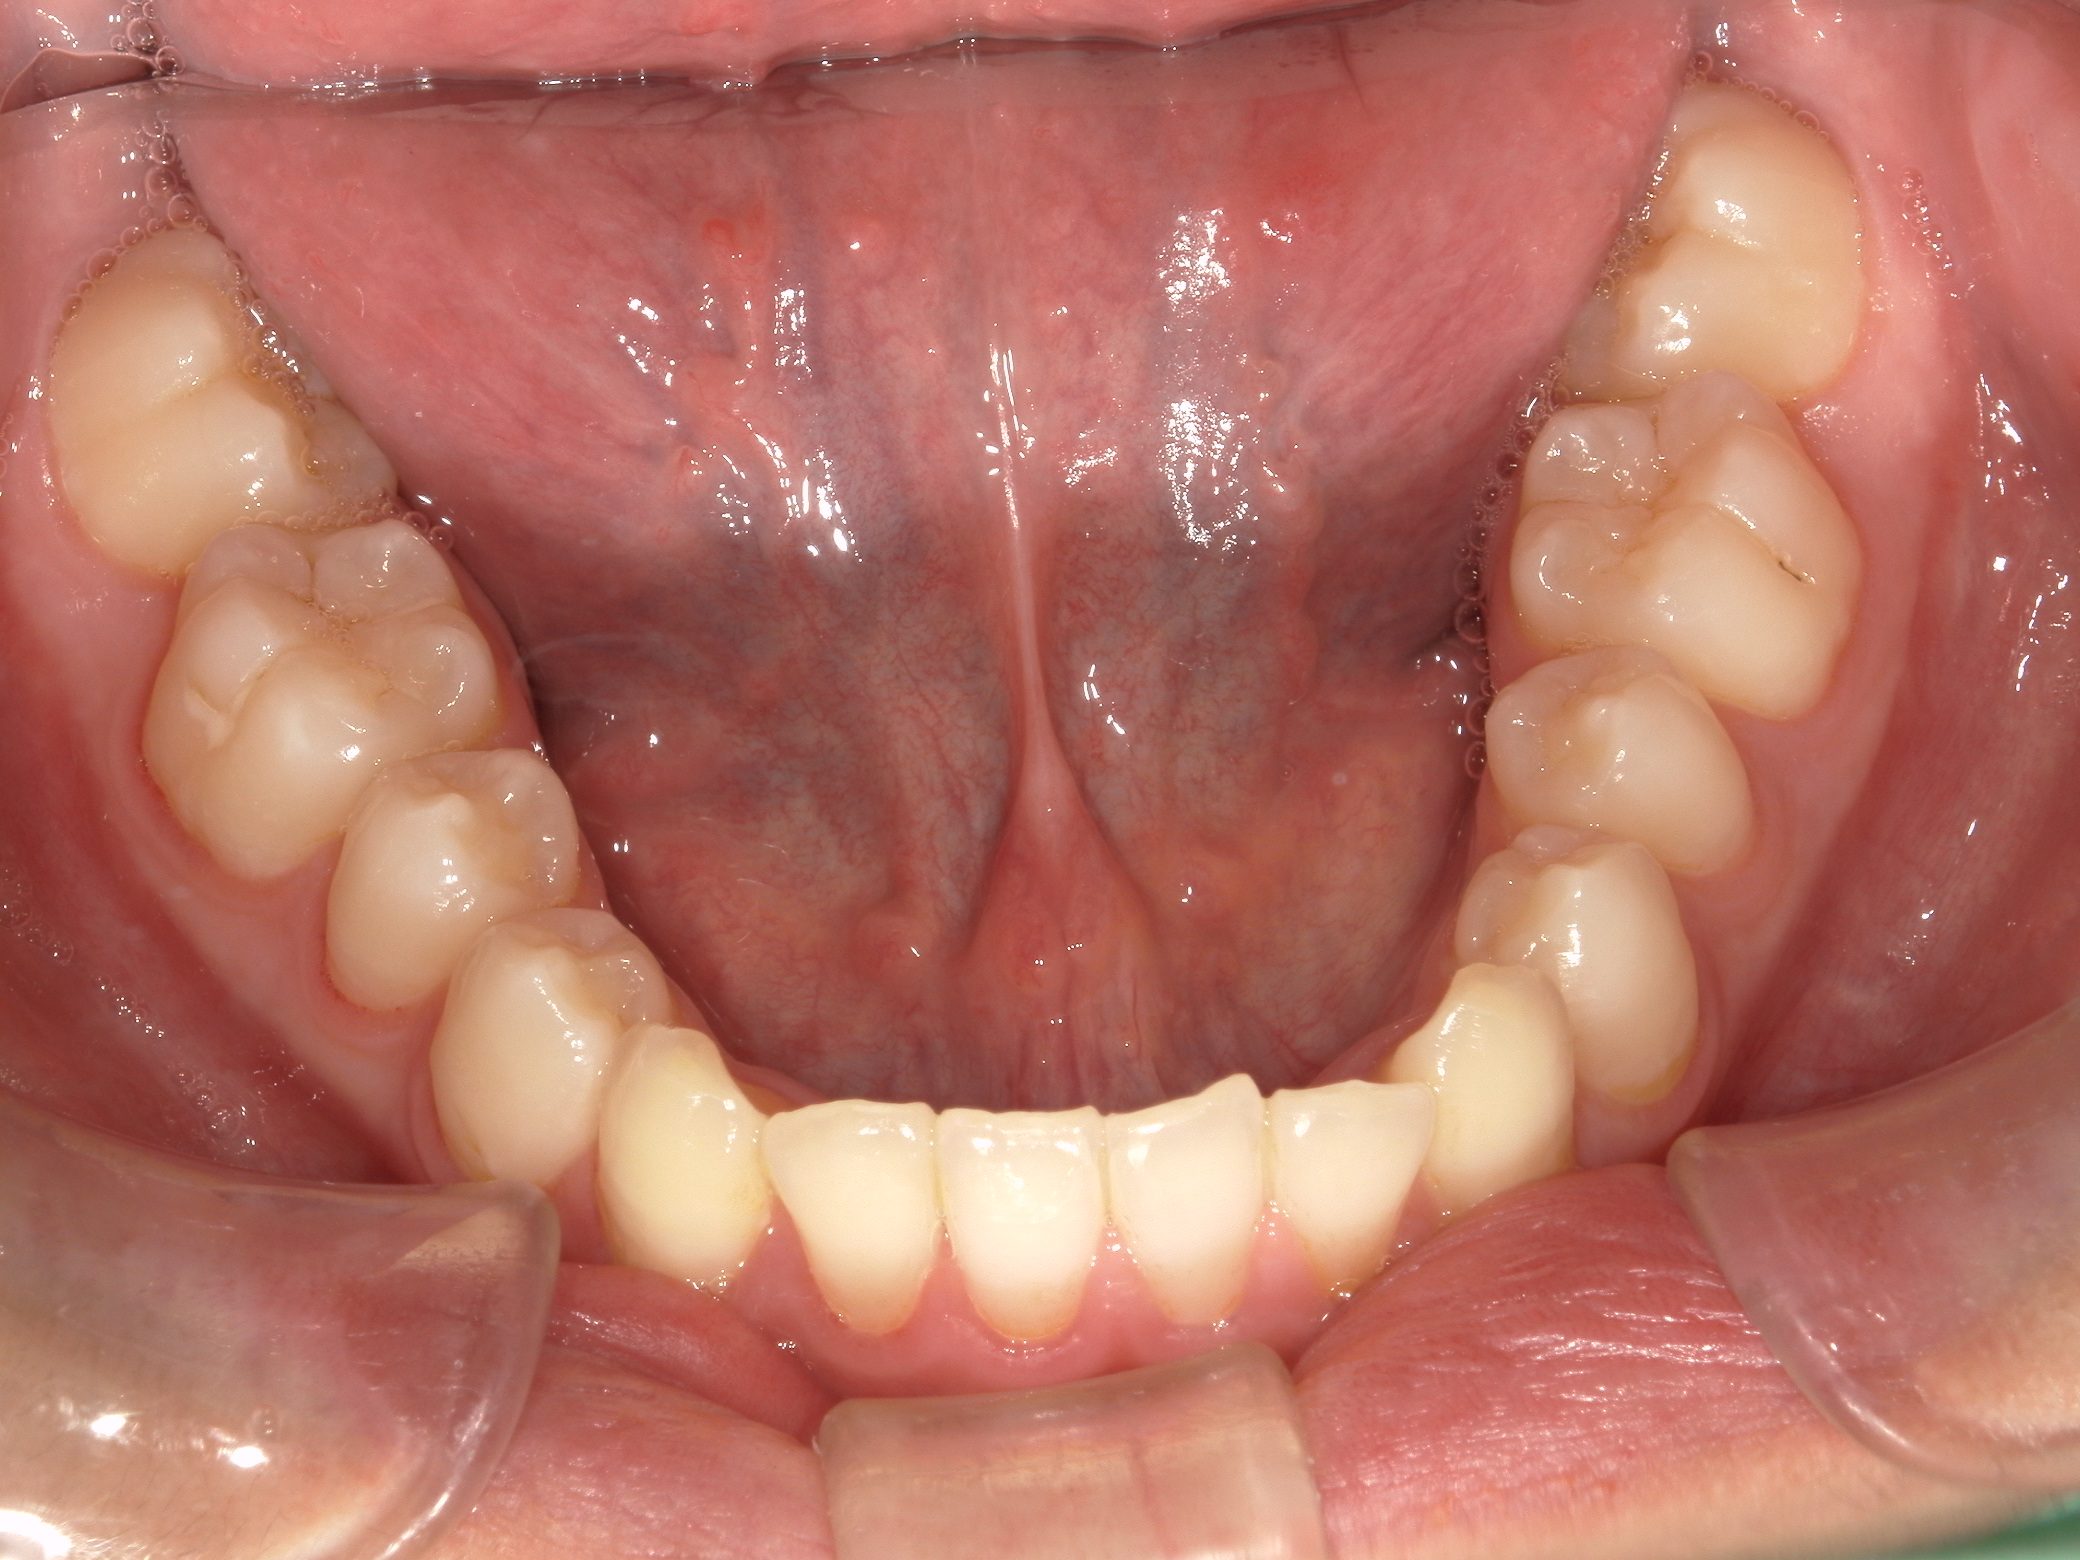

Before

After

治療期間

10か月年

治療開始

19歳

種類

インビザライン矯正

使用装置

インビザラインフル

コメント

すきっ歯なので ディスキングなどもなし

県外の大学に進学されていたので2カ月ごとの来院で10か月で終了

一番奥の歯がすれ違い咬合でしたが、綺麗に治りました。